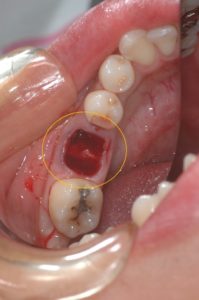

抜歯を行いました。しかしながら、これでは移植する歯が入りません。そこで、抜歯窩の骨を削合して親知らずを移植します。

抜歯窩の骨を削合しました。